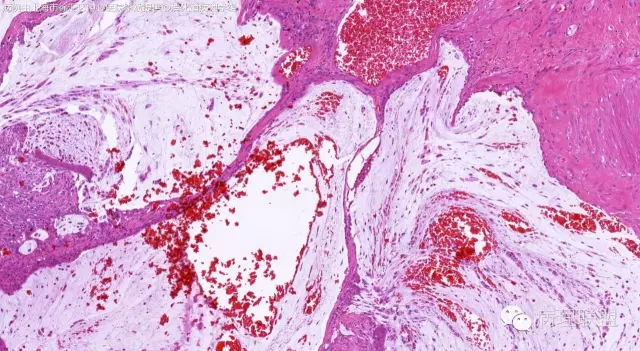

男,64岁,距肛门口45cm息肉大体:灰白结节2*2*1cm(病例由上海市徐汇区中心医院 李斌 提供,致谢!)

管状~绒毛状腺瘤伴低级别上皮内瘤变,黏膜下层部分腺体破裂黏液外溢伴黏液糊形成。

本例部分腺体异位到黏膜下层。

@李斌 李大夫的片子一向漂亮,有赏心悦目的感觉,必须赞一个。这例同意周大夫的意见,低级别绒毛管状腺瘤伴腺体破裂导致的黏液外溢。粘液池周围可见血管扩张淤血、含铁血黄素沉积、肉芽组织形成,提示发生过蒂扭转和出血,这常是造成假浸润、粘液溢出的原因。比较大的绒毛管状腺瘤会有分叶结构,会有比较粗大的平滑肌干,但缺少P-J息肉叶脉样从主干再分支出来的细平滑肌束。作为错构瘤性息肉的一种,P-J息肉的腺体可以分支、扩张、腺腔不规则,但没有细胞异型性,伴发异型增生时,局部出现细胞异型性但不会像这例这样齐刷刷都是异型的腺体。